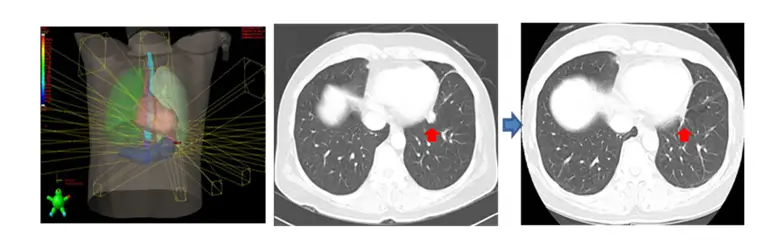

호흡주기 맞춤형 4차원 CT 영상을 이용하여 치료 계획을 만들고 치료에 응용하는 호흡동기방사선치료 (Respiratory-gated Radiation Therapy)를 시행하고 있습니다. 방사선치료 중 환자는 평소와 같이 편안하게 호흡을 하고 있으면, 영상장치를 이용하여 종양이 가장 적게 움직이는 호흡주기에만 선택적으로 방사선을 치료하는 방법입니다.

체부 정위적 방사선치료 (SBRT; Stererotactic Body Radiation Therapy)